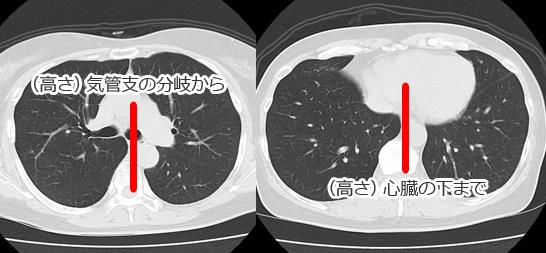

1. 気管分岐の開大

2. 心右縁下部の内側に見られる二重陰影(double density)

3. 心腰の突出

4. 胸部下行大動脈の左外側への圧排

側面像:

1. 左気管支の上方への圧排

2. 心後縁上部の後方への限局性圧排